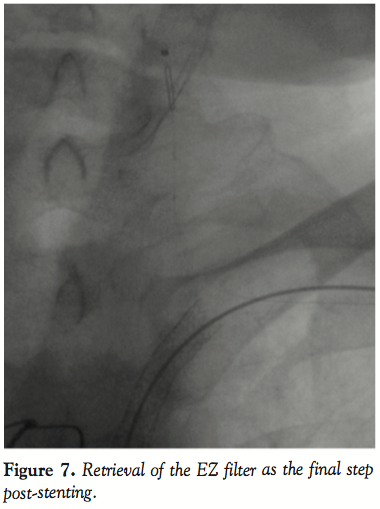

A 0.014˝ Choice PT graphix guidewire (Boston Scientific Corporation) was passed through the SC lesion via the transbrachial route with some difficulty. The guidewire was then advanced down into the iliac artery and pulled out of the femoral introducer using a GooseNeck snare (ev3, Inc., North Plymouth, Minnesota) (Figures 3 and 4). The wire was then introduced within a 5 Fr, 11 cm pediatric sheath (Cordis Corporation, Miami, Florida). A 5 Fr multipurpose guiding catheter (GC) was later advanced over the 0.014˝ wire and positioned just near the ostium of the left SC artery. The lesion was then predilated with a 2 x 20 mm and then a 3 x 20 mm Maverick balloon (Figure 5). Only then could the GC advance across the distal portion of the vessel to the lesion. At this moment, the 0.014˝ wire was removed and exchanged for a 0.035˝ wire (260 cm in length) through the GC. Then, the 5 Fr introducer femoral sheath was  exchanged for a 7 Fr, 61 cm SL2 sheath (St. Jude Medical, Daig Division, Minnetonka, Minnesota) positioned just near the ostium of the left subclavian and subsequently a 7 x 37 mm Express LD stent (Boston Scientific Corporation) was deployed in situ (Figure 6). Advancement of the GC across the lesion after predilation as well as all inflations within the SC artery were protected with prior LIMA 2.5 mm balloon inflation at 6 atm with subsequent deflation 5 seconds after deflating the subclavian balloon or stent. Post-dilatation of the stent was not performed. The LIMA balloon was withdrawn, then the Filterwire was retrieved with its  retrieval sheath (Boston Scientific Corporation) through the brachial sheath without any difficulty (Figure 7). The patient tolerated the procedure well and there were no complications. Some debris was retrieved in the Filterwire.